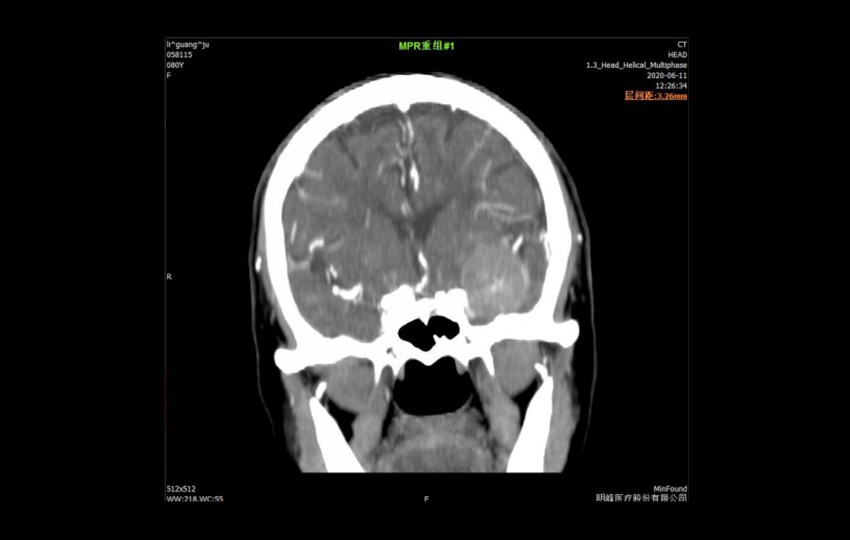

1-1<br>Méningiome

Méningiome